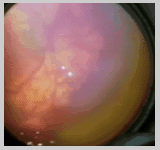

Para hacer un diagnóstico clínico de Zona I, realizamos

el examen de fondo de ojo con una lupa de 28 Dioptrías y

si dentro del mismo campo de visión podemos observar la papila

en un extremo y el límite entre la retina vascular y avascular

en el otro podemos afirmar que nos encontramos frente a una retinopatía

en zona I (Foto). Si utilizamos una lupa de 20 dioptrías,